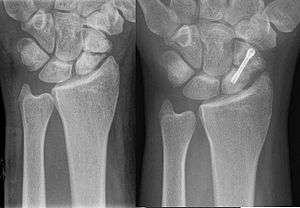

A more obvious scaphoid fracture on a scaphoid view X ray

Non displaced or minimally displaced waist and distal fractures have a high rate of union with closed cast management. The choice of short arm, short arm thumb spica or long arm cast is debated in the medical literature and no clear consensus or proof of the benefit of one type of casting or another has been shown; although it is generally accepted to use a short arm or short arm thumb spica for non displaced fractures. Non displaced or minimally displaced fracture can also be treated with percutaneous or minimal incision surgery which if performed correctly has a high union rate, low morbidity and faster return to activity than closed cast management.[7] Percutaneous screw fixation is recommended over a wide surgical approach as this method preserves the palmar ligament complex and local vasculature, and helps avoid postoperative complications. This surgery includes screwing the scaphoid bone back together at the most perpendicular angle possible to promote quicker and stronger healing of the bone. During this procedure, slight excavation of the edge of the trapezium bone may be necessary to reach the scaphoid as 80% of this bone is covered with articular cartilage, which makes it difficult to gain access to the scaphoid.[8]